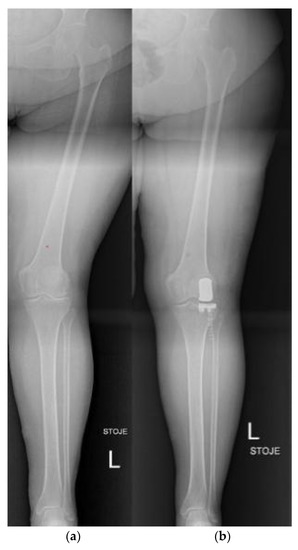

3.6. Knee

- Wolcott, M.; Traub, S.; Efird, C. High Tibial Osteotomies in the Young Active Patient. Int. Orthop. 2010, 34, 161–166. [Google Scholar] [CrossRef] [PubMed]

- Gomoll, A.H. High Tibial Osteotomy for the Treatment of Unicompartmental Knee Osteoarthritis: A Review of the Literature, Indications, and Technique. Phys. Sportsmed. 2011, 39, 45–54. [Google Scholar] [CrossRef] [PubMed]

- Saragaglia, D.; Sigwalt, L.; Rubens-Duval, B.; Chedal-Bornu, B.; Pailhe, R. Concept of Combined Femoral and Tibial Osteotomies. J. Knee Surg. 2017, 30, 756–763. [Google Scholar] [CrossRef]